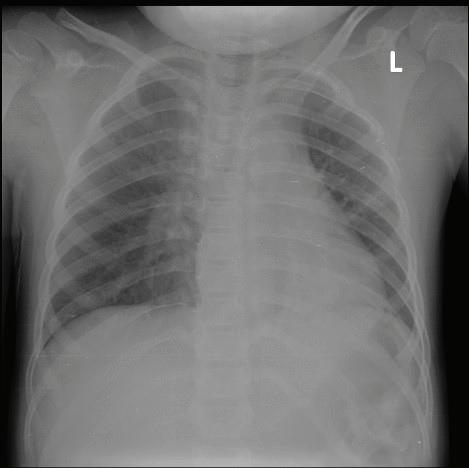

паренхим и КАТ на глава – без данни за патологични отклонения. Предвид липсата на корелация между тежкото клинично състояние и несигнификантно изменените параклиникнични показатели – рентгенография без патологични отклонения - се проведе КАТ на бял дроб. От КАТ на бял дроб се установява образ, който на рентгенографията не се визуализира: възпалителен инфилтрат в 10 сегмент вляво с тенденция към консолидация и дилатирани съдове, вероятна хиперемия. Единични медиастинални лимфни възли, Фиг. 1 и Фиг. 2

Фиг. 1 Рентгенография бял дроб

Фиг. 2 КТ гръден кош